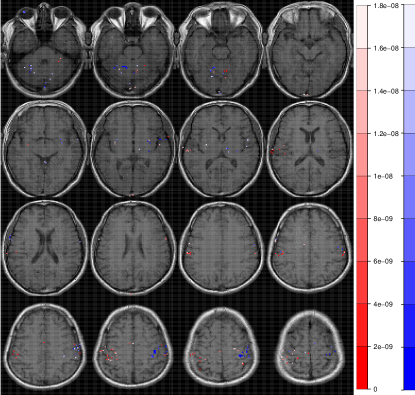

Refer to caption

Figure 2: Radiologic view maps of observed p𝑝p-values of activation of the t𝑡t-test of motor function for (a) the right-hand and (b) left-hand finger-thumb opposition task experiments. For each set of experiments, we display radiologic view maps for the 18th, 19th, 20th and 21st slices (row-wise). The twelve replications are represented column-wise from 1 through 12. For each slice, we display the p𝑝p-values of activation for the thresholded voxels using a t𝑡t-test of the motor function for the twelve replications of the finger-thumb opposition experiment performed by (a) the right hand and (b) the left hand of the same right-hand dominant male volunteer. Note the differences in location and extent of activation over the twelve replications. Note, also the substantial more variability in the experiments performed by the subject’s left hand than on the right.

Figure 2 represents the observed p𝑝p-values of activation for slices 18, 19, 20 and 21 (row-wise) over the twelve replications for both the (a) right-hand and (b) left-hand finger-thumb opposition tasks. (All displayed maps in this paper are in radiologic views and overlaid on top of the corresponding T1fragmentsT1\mbox{T}_{1}-weighted anatomical images.) The specific slices were chosen for display because they encompass the ipsi- and contra-lateral pre-motor cortices (pre-M1), the primary motor cortex (M1), the pre-supplementary motor cortex (pre-SMA), and the supplementary motor cortex (SMA). Clearly, there is some variability in the results for the right-hand task. In Figure 2a for instance, all experiments identify activation in the left M1 and in the ipsi-lateral pre-M1 areas, but there is some modest variability in the identified activation in the contra-lateral pre-M1, pre-SMA and SMA voxels, with some experiments reporting very localized or no activation and others having these regions as activated and somewhat diffused in extent. Slices for the left-hand finger-thumb opposition task experiments in Figure 2b, on the other hand, show far more variability, both in location and extent. It is interesting to note that while most experiments identify activation in the right M1, the ipsi-lateral, contra-lateral pre-M1, pre-SMA and SMA areas, they also often show activation in the corresponding left regions. The case of the eighth replication is extremely peculiar. Most of the activity in the four slices are in the left areas and the right areas have little to no activation. This makes one wonder if the naturally right-hand dominant male volunteer had, perhaps unintentionally and out of habit, used his right hand instead of his left in performing some part of the experimental paradigm. In summary, there is clearly far more variability in the left hand set of experiments than in the right hand set. We now assess the reliability in each set separately.